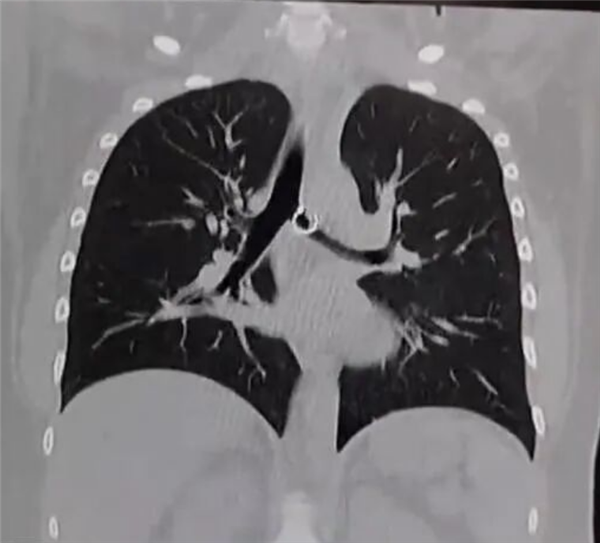

据悉,莫妮卡最初将咳嗽归咎于普通感冒,并未重视,期间发现佩戴的鼻环丢失,也只当是无意中掉落,从未将两者关联。直到咳嗽持续一个月,甚至影响正常生活,她才就医检查,X光和CT扫描清晰显示,其肺部有一枚金属异物,正是她丢失的鼻环。医生检查后直言情况极度危险,鼻环已深深嵌入肺部组织,一端的金属小球距离肺主动脉仅0.5毫米,一旦移位或被触碰,就可能刺破主动脉,导致瞬间大出血,几乎没有抢救时间。